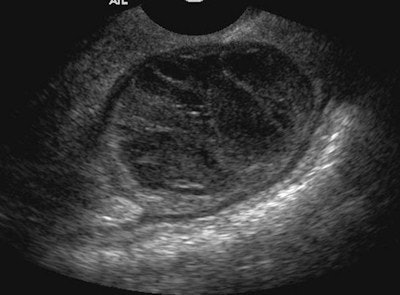

| Endometrioma: Patient presented to the emergency department with lower abdominal pain that became worse during menstruation. Subsequent transvaginal ultrasound demonstrated heterogeneous echotexture. Hypoechoic regions are a result of organizing hemorrhagic debris within hyperechoic septations and wall foci. Anechoic cysts may occur, but they are rare. All images courtesy of Dr. Óran Roche. |